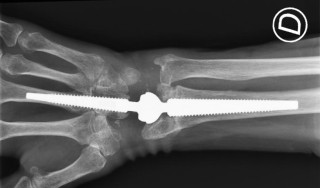

FM1

Lessons learned: 20 MOTEC® over 4 years

Léonie Hüsler, Luzern

Léonie Hüsler1, Carla Kellenberger2, Stefanie Schmitt2, Urs Hug2 (1Luzerner Kantonsspital, Chur; 2Luzerner Kantonsspital, Luzern)

Einführung

Die Handgelenksprothetik hat über Jahrzehnte und mehrere Implantatgenerationen hinweg unzufriedenstellende Resultate geliefert und wird aufgrund der fehlenden Langzeitergebnisse der neuesten Generation weiterhin skeptisch beurteilt. Mit der Entwicklung der MOTEC® Prothese, die sich durch eine stabile Verankerung im dritten Mittelhandknochen auszeichnet, hat sich eine neue Begeisterung eingestellt, welche durch die publizierten Studienergebnisse von Reigstad et al. verstärkt wurde.

Methodik

Retrospektive Analyse von 21 MOTEC®-Prothesen, implantiert durch den Senior-Autor zwischen Oktober 2020 und März 2025. Eingeschlossen wurden 20 Patienten (15 Männer, Ø Alter zum Zeitpunkt der Operation betrug 63 Jahren) mit posttraumatischer Arthrose, vorwiegend SLAC-wrist.

Ergebnisse

PROMs und CROMs wurden erhoben und bewegen sich im publizierten Rahmen. Mit Fokus auf generelle Probleme und Komplikationen sind folgende Punkte erwähnenswert:

- Intraoperative Perforationen des dritten Mittelhandknochens (1), des Radius (1) sowie Berstungen des Capitatums (2) – ohne Einfluss auf das postoperative Management

- Limitierte intraoperative Platzverhältnisse bedingt durch vorgängige PRC erforderte einen palmaren Kapselrelease (3)

- In der ersten Fallserie zeigte sich postoperativ eine deutliche Schwellungstendenz; das postoperative Management wurde mit einer Kortisonstosstherapie ergänzt

- Wundheilungsstörung (1)

- Periprothetische Ossifikation mit Impingement (1), Revision steht an

- Periprothetische Radiusfraktur (1) nach Sturz

- Postoperativer Hochstand des Kopfes des dritten Mittelhandknochens (2)

- Beobachtete Tendenz zur Flexionsstellung und Ulnardeviation des Handgelenkes

- Schlechtere Beweglichkeit nach vorgängiger PRC im Vergleich zu Patienten ohne PRC (durchschnittlicher Bewegungsumfang Flexion-Extension von 58° vs. 105°)

Schlussfolgerung

Mit strenger Indikationsstellung, Konzentrierung der Erfahrung auf einen Operateur und einem kurzen Nachbeobachtungszeitraum von maximal 2 Jahren zeigen sich in 21 mit MOTEC® versorgten Handgelenken gute bis sehr gute Resultate. Nur in einem Fall steht eine Revision mit Erhalt des Implantates an. Gewisse Probleme wie Schwellungstendenz oder schlechtere Beweglichkeit nach früherer PRC sind in die präoperative Aufklärung und Planung miteinzubeziehen. Aufgrund der sehr hohen Patientenzufriedenheit und der bisherigen vielversprechenden Studienlage beabsichtigen wir, die Implantation der MOTEC® weiterhin selektiv einzusetzen.